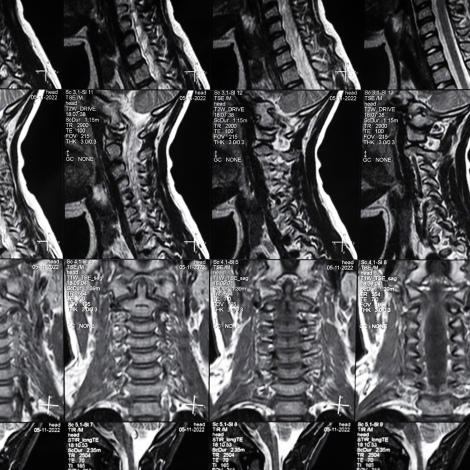

Cervial Spine MRI

Your doctor may recommend an MRI to better diagnose or treat problems with your spine like injury-related pain, severe neck ache, radiculopathy, infection, tumor, demyelination, birth defects etc.